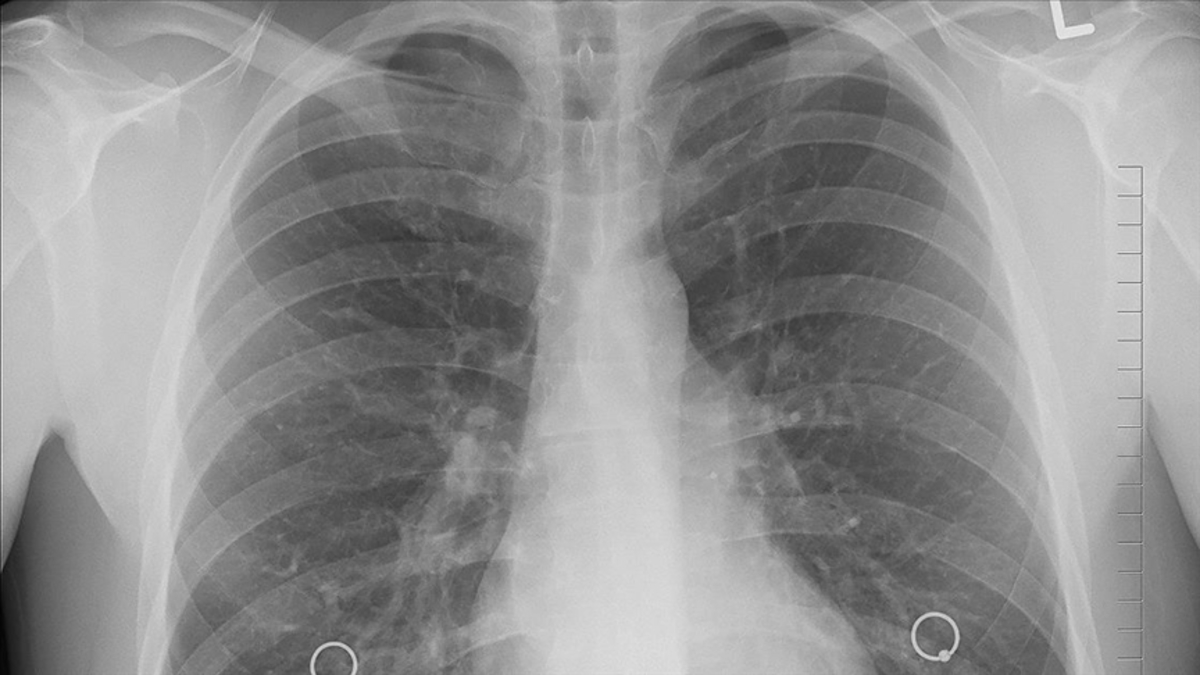

Standart akciğer röntgenlerinin belli boyuttan küçük lezyonları göstermede yetersiz kalabildiğine değinen Uzm. Dr. Cengiz Şen, "Lezyon ne kadar büyürse metastaz yapma olasılığı artacak ve tedavi başarısı düşecektir. Yapılan çalışmalar herhangi bir şikâyeti olmayan ancak sigara içtiği için risk grubunda olan insanlarda her yıl düşük doz akciğer tomografisi çekilerek yapılan tarama programının erken teşhis oranlarını artırdığını ve ölüm oranlarını azalttığını göstermiştir. Akciğer kanseri ne kadar erken evrede yakalanırsa tedavi şansı da o oranda yüksektir. Tedavideki temel yaklaşım kanserli dokunun tamamen ameliyatla çıkarılmasıdır. Bir santimden küçük evre 1 akciğer kanserinde tümör dokusu cerrahi olarak çıkarıldığında tedavi şansı yüksek oranlara çıkabilmektedir. Ameliyat sonrası veya öncesi hastalığın yayılımına göre radyoterapi ve/veya kemoterapi yapılabilmektedir. Ameliyat şansı olmayan hastalarda radyoterapi ve kemoterapi uygulanabilir. Kemoterapi dışında son yıllarda kullanılmaya başlanan immünoterapi ve akıllı moleküller grubunda bazı ilaçların da yaşam süresini uzattığı hatta kemoterapiye kıyasla hem daha etkili hem de yan etkilerinin daha az olduğu gösterilmiştir. Mutasyonu hedefleyen akıllı moleküllerin kullanımı için kanser dokusunda bazı genetik mutasyonların varlığını tespit etmek gerekmektedir" dedi.